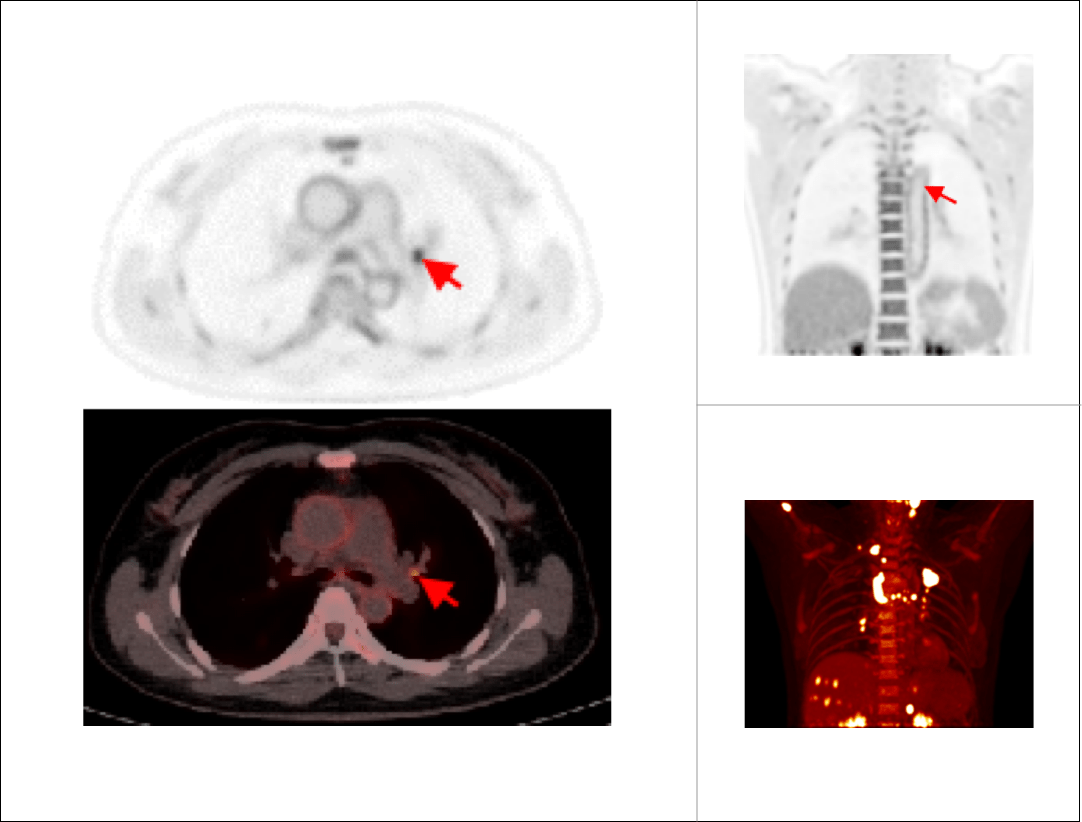

肺癌胸腹部单床位大范围延迟扫描